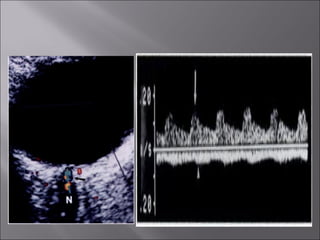

Ultrasound and CT scans provide anatomical images of the orbit, while color Doppler imaging provides visualizations of vascular structures and blood flow within lesions. These imaging techniques are used to evaluate a variety of orbital conditions involving blood vessels, infections, tumors, congenital issues, trauma, and more, and can help identify vascular disorders, thrombosis, treatment responses, and dynamic changes in benign tumors over time.